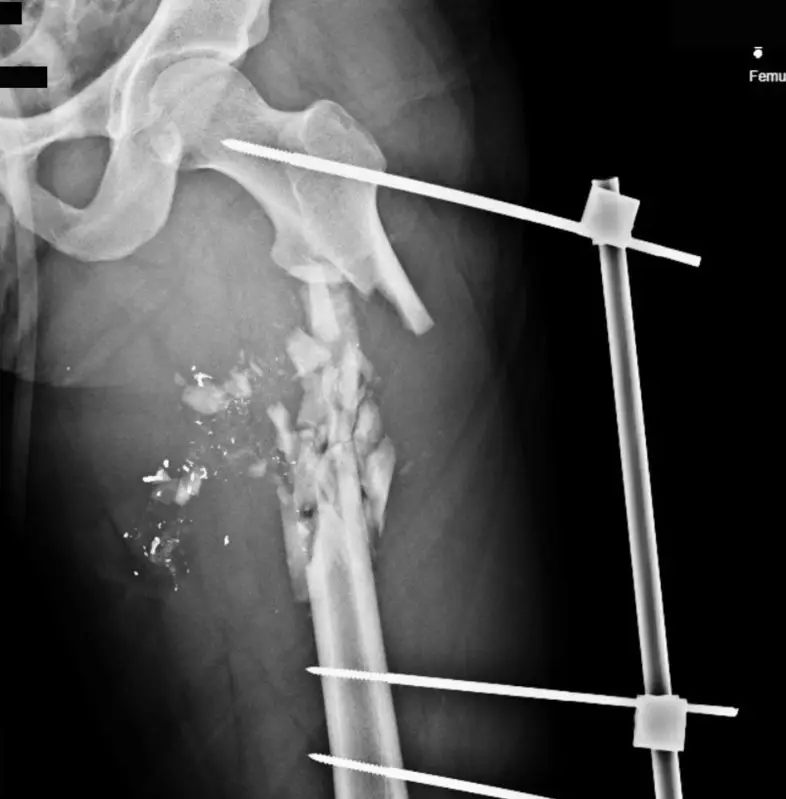

وأظهرت هذه الصور التي تجاوز عددها 75 فحصا بالأشعة السينية والتصوير المقطعي، أنماطا مروعة من الإصابات الناجمة عن استخدام بنادق هجومية وطلقات صيد معدنية ضد المحتجين.

وأظهرت الفحوصات إصابات قاتلة أخرى بينها رصاصة كبيرة العيار استقرت في دماغ رجل منتصف العمر، وأخرى مزقت القصبة الهوائية لشاب إضافة إلى إصابات في العمود الفقري والصدر والرئة.

وأكد الخبراء الذين راجعوا هذه الوثائق أن النمط المتكرر للإصابات يشير إلى استهداف مباشر لمناطق حيوية مثل الوجه والصدر والأعضاء التناسلية، وهو ما يعكس نية متعمدة لإحداث إعاقات دائمة.